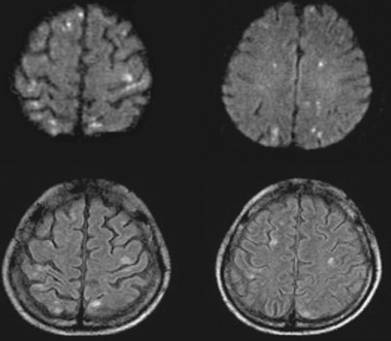

Hình 2